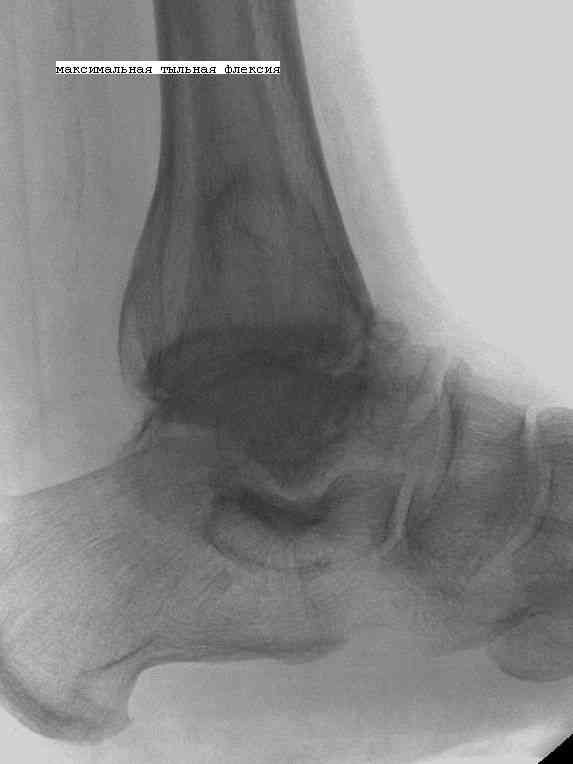

К нам обратился пациент 73 лет с жалобами на боли и деформацию в области левого голеностопного сустава.

В анамнезе: в 1980 году перелом обеих лодыжек с вывихом стопы кнаружи. Лечился консервативно: одномоментная репозиция переломовывиха в левом голеностопном суставе с трансартикулярной фиксацией голеностопного сустава спицами Киршнера через пяточную, таранную, большеберцовую кости. Накладывалась гипсовая иммобилизация. Даная манипуляция осложнилась нагноением с развитием гнойного артрита. Были удалены спицы, сустав со слов больного, промывался растворами, но не вскрывался, получал антибиотики. Гнойный процесс был купирован, и рецидива с тех пор не было.

Об-но: Левый голеностопный сустав деформирован за счет разрастания костной ткани и отечности мягких тканей. Левая стопа с вальгусной установкой, практически отсутствуют все своды левой стопы (стопа плоская). Полный объем движений в левом голеностопном суставе максимум достигает 15 гр, движения стопы в основном за счет подтарнного сустава. Пальпаторно область голеностопного сустава не столь болезненна, как болезненна область подтаранного сустава и область таранно-ладьевидного сустава.

После изучения объективного статуса, анамнеза, рентгенснимков, больному предложен был трехсуставной артродез, так-как мы сочли это наиболее приемлемым в данном случае. Но больной отказывается от данной операции и настаивает на эндопротезировании левого голеностопного сустава. Во первых, наше отделение не имеет опыта в эндопротезиовании голеностопного сустава. Во вторых, нам кажется, что трехсуставное артродезирование в данном случае наиболее подходящее. Причиной тому, на наш взгляд, выраженная деформация левой таранной кости, как следствие аваскулярного некроза, и то что болит не голеностопный сустав в данном случае ( хотя в нем и ограничено движение), а подтранный и таранно-ладьевидный суставы и то что эндопротезирование одного голеностопного сустава не решит проблем в подтаранном, ладьевидно-таранном сочленениях. Наши доводы оказались безуспешными, а так как пациент является ученным, требовал доказательной базы наших умозаключений.